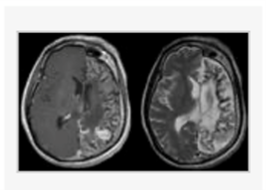

A five-year-old right-handed boy has had medically intractable epilepsia partials continua for 4 years. Evaluation demonstrates developmental delay, worsening of verbal IQ and right-sided hemiparesis. EEG demonstrate several epileptogenic foci over the left parietal lobe. MRI imaging is shown. Aside from invasive monitoring, which of the following is the most appropriate surgical treatment? a. Vagus nerve stimulation b. Corpus callosotomy c. Functional hemispherectomy d. Parietal lobectomy e. Selective amygdalohippocampectomy

c. Functional hemispherectomy